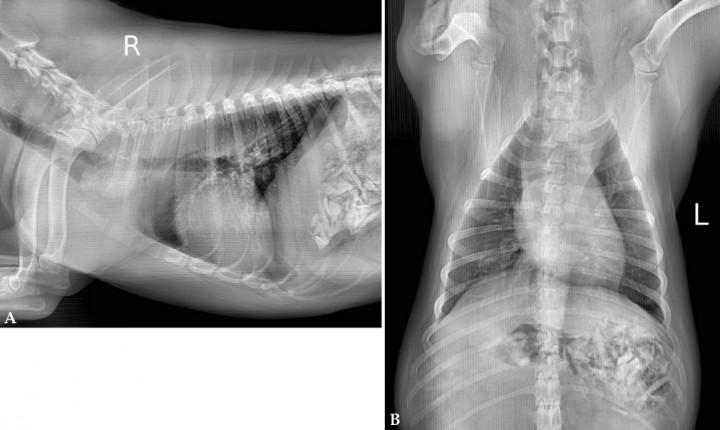

Se realizó un estudio radiográfico con contraste yodado (Fig. 3) para confirmar la presencia de un CE y valorar si había perforación esofágica. El contraste administrado [Ultravist 300 mg/ml (Bayer AG, Berlín), dosis 1 ml/kg VO] se acumulaba en el esófago cervical, creándose un defecto de llenado en la zona craneoventral del esófago torácico. Parte del contraste pasaba a esófago caudal. No se observó contraste libre en el tórax lo que descartaba la presencia de perforación esofágica. En este caso la historia clínica y la imagen radiográfica permitieron obtener un diagnóstico de obstrucción esofágica por CE, específicamente hueso. Un estudio endoscópico ayudaría a identificar la naturaleza del cuerpo extraño, además de ser una opción terapéutica. En este caso se realizó un estudio endoscópico que permitió confirmar que el CE esofágico era un hueso. No fue posible la extracción de mismo por esta vía debido a su gran tamaño, procediéndose a su extracción por cirugía torácica convencional.

<p>Radiografía de la cavidad torácica en proyección lateral derecha, tras la administración de contraste yodado vía oral, en la que se evidencia cómo la columna de contraste se detiene craneal al cuerpo extraño (CE) esofágico, aunque se puede observar que hay paso de un poco de contraste tras el CE, dorsal a la tráquea y la silueta cardíaca.</p>

Figura 3

Radiografía de la cavidad torácica en proyección lateral derecha, tras la administración de contraste yodado vía oral, en la que se evidencia cómo la columna de contraste se detiene craneal al cuerpo extraño (CE) esofágico, aunque se puede observar que hay paso de un poco de contraste tras el CE, dorsal a la tráquea y la silueta cardíaca.